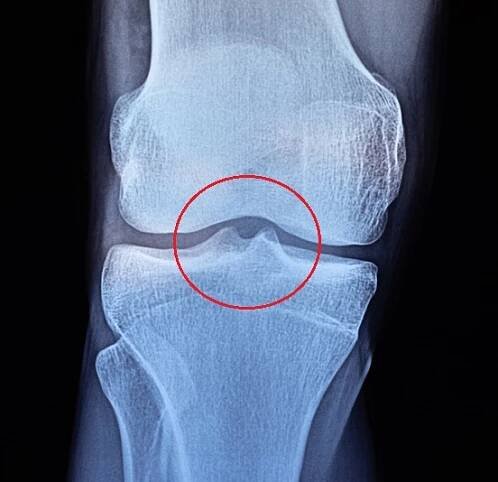

osteoidní osteom, benigní kostní nádor.

Tento obrázek ukazuje osteoidní osteom pozorovaný pod mikroskopem.

Osteoidní osteom je benigní nádor projevující se noční bolestivostí, která příznivě reaguje na acylpyrin. Vyskytuje se v koriové části kosti, kde edémem kolem sebe působí bolesti okostice.